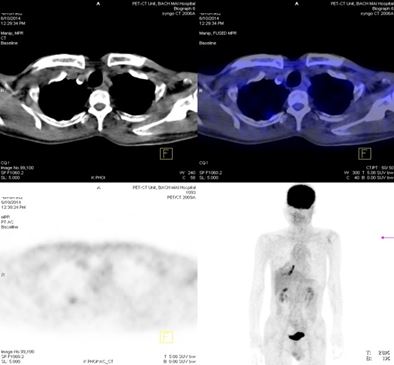

Trước điều trị: Hạch thượng đòn phải 1,1cm, max SUV=5,67; Hạch thượng đòn trái 0,8cm, max SUV=3,97.

Sau điều trị: Không thấy hạch thượng đòn

Trước điều trị: Tổn thương cung sau xương sườn số 2 bên phải, giá trị max SUV=3,13.

Sau điều trị 4 tháng: Không có bất thường

Đánh giá sau 4 tháng điều trị: Bệnh nhân đáp ứng hoàn toàn, lâm sàng cải thiện tốt, khối u và các hạch, cơ quan khác di căn tan biến. Tuy nhiên, trong quá trình bệnh nhân sử dụng thuốc, xuất hiện nổi ban ngoài da vùng mặt, ngực mức độ nhẹ. Bệnh nhân tiếp tục được duy trì Iressa 250 mg uống 1 viên / ngày.

8.Đánh giá sau 9 tháng điều trị:

Lâm sàng đáp ứng tốt, bệnh nhân không còn nổi ban ngoài da, chụp PET/ CT đánh giá lại sau 9 tháng điều trị kết quả: khối u phổi phải không còn, không còn hạch di căn, các vị trí di căn tại gan, xương biến mất.